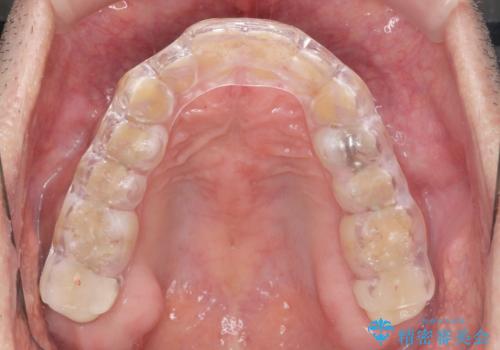

歯ぎしり いびきに効果的なスプリントナイトガード

歯ぎしりが気になる。